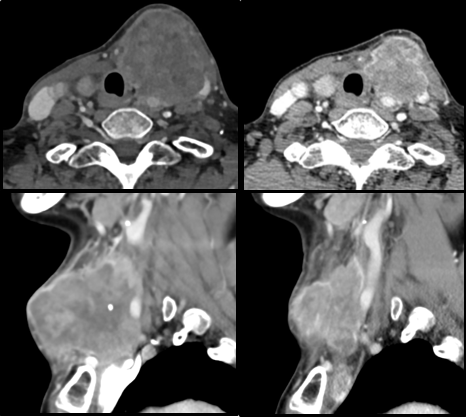

患者予以盐酸安罗替尼 12mg/天,连用两周休息一周,共治疗2个疗程,评估疗效为PR。

靶向前                        靶向后